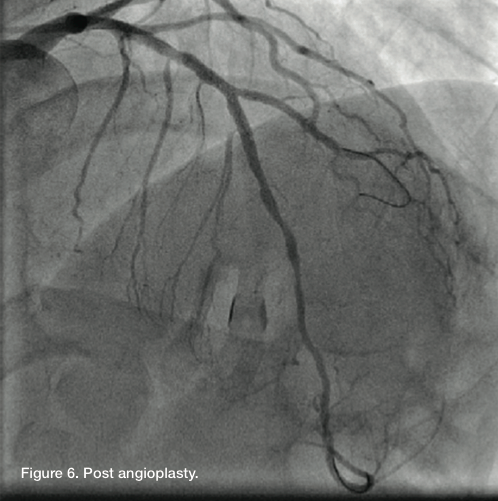

A Runthrough wire was advanced into the diagonal and a second Runthrough wire advanced distally into LAD. The Wiggle wire was removed. Kissing balloon angioplasty of the LAD and diagonal was performed. A 2.5 x 12

mm Apex balloon (Boston Scientific) was advanced into the diagonal and another 2.5 x 12 mm Apex balloon into the LAD. We inflated the diagonal at 6 atm, came down and then did kissing balloon inflation at 8 atm in both vessels. There was an excellent angiographic result, with TIMI-3 flow in both vessels and a residual of less than 20% in the ostial diagonal.